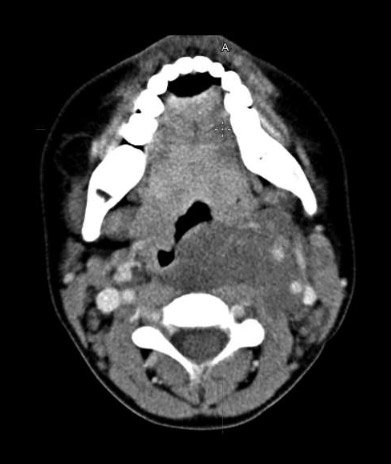

По результатам КТ (рис.): КТ-картина распространения опухолевых масс глотки слева на мягкие ткани шеи с инфильтрацией левой доли щитовидной железы, периваскулярным распространением на ретрофарингеальное, висцеральное, каротидное пространства шеи, преимущественно слева, с прорастанием кольца трахеи по левой окружности. Метастазы в лимфатические узлы шеи Ia, IIa групп.

Рисунок. КТ шеи в аксиальной проекции, контрастное усиление

По данным МРТ: МР-признаки образования левого парафарингеального пространства с распространением в ретрофарингеальное, висцеральное, каротидное, заднее шейное пространства, преимущественно слева с прорастанием кольца трахеи по левой полуокружности, с вовлечением общей сонной артерии, внутренней сонной артерии, наружной сонной артерии, позвоночной артерии. Метастазы в л/у шеи Iа, IIа групп. МР- признаки образования слева на уровне сегмента 5–6 грудных позвонков с распространением в мягкие ткани спины.